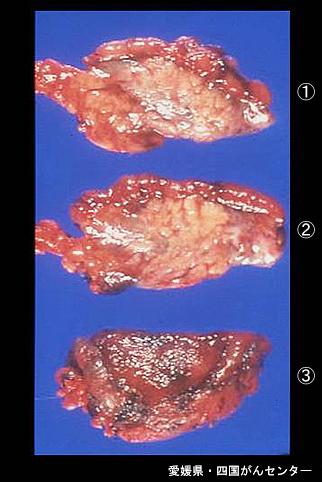

Posted by: Ehime Pref., 四国癌中心 (Dr. 平崎)

疾病(病理主体)的分类肿瘤样病变/异位粘膜

部位(按器官分)胃(部位)/胃角

检查方法切除标本(宏观)

肿瘤最大直径40以上